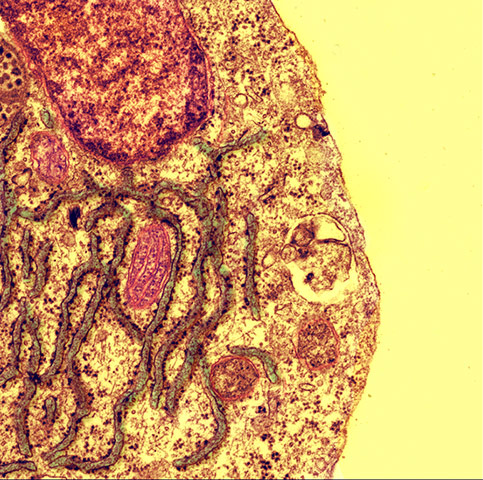

Shortlisted: Rough Road to Regeneration by Andrea Caporali, University of Bristol. This scanning-electron microscope image shows the stress response of a blood vessel cell in a condition such as diabetes. Understanding the stresses that diabetes places on the cardiovascular system may help researchers treat some of its complications Photograph: Andrea Caporali/University of Bristol/The British Heart Foundation